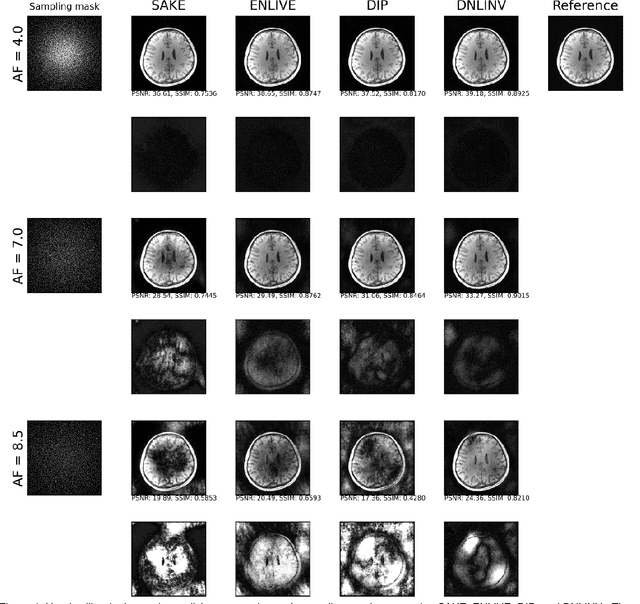

Magnetic resonance imaging is subject to slow acquisition times due to the inherent limitations in data sampling. Recently, supervised deep learning has emerged as a promising technique for reconstructing sub-sampled MRI. However, supervised deep learning requires a large dataset of fully-sampled data. Although unsupervised or self-supervised deep learning methods have emerged to address the limitations of supervised deep learning approaches, they still require a database of images. In contrast, scan-specific deep learning methods learn and reconstruct using only the sub-sampled data from a single scan. Current scan-specific approaches require a fully-sampled auto calibration scan region in k-space that cost additional scan time. Here, we introduce Scan-Specific Self-Supervised Bayesian Deep Non-Linear Inversion (DNLINV) that does not require an auto calibration scan region. DNLINV utilizes a deep image prior-type generative modeling approach and relies on approximate Bayesian inference to regularize the deep convolutional neural network. We demonstrate our approach on several anatomies, contrasts, and sampling patterns and show improved performance over existing approaches in scan-specific calibrationless parallel imaging and compressed sensing.